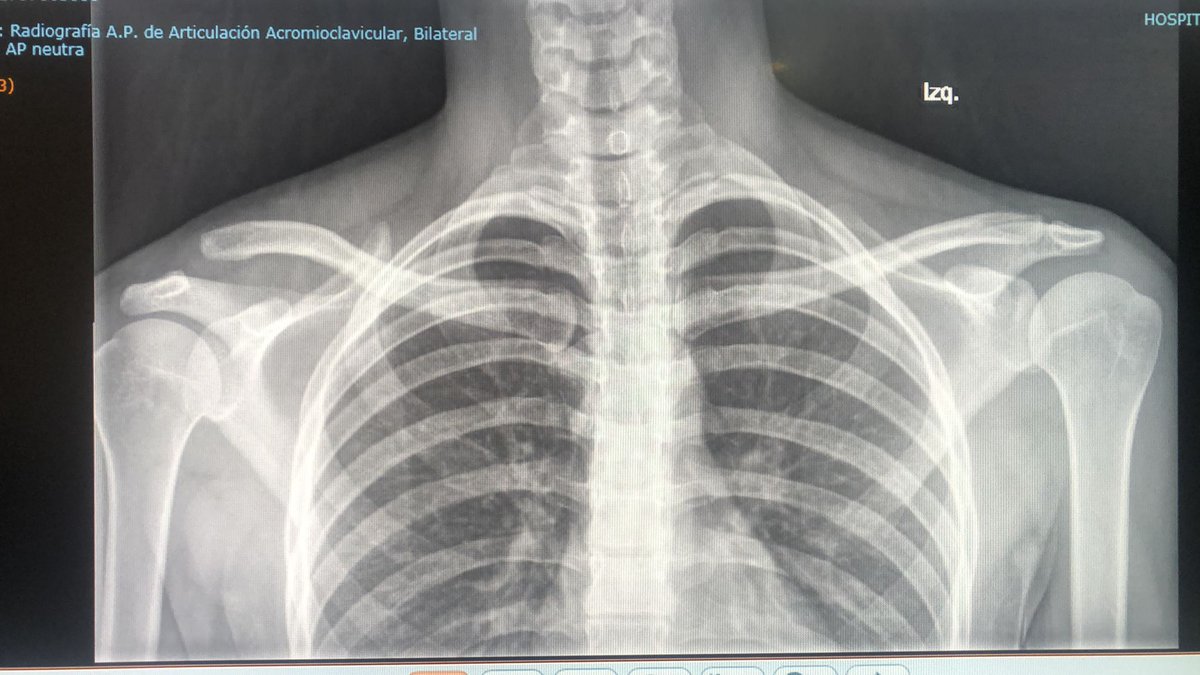

Midshaft #clavicle nonunion prediction at 6 wks post-injury appears superior to time of injury. We found 3 simple clinical predictors can accurately predict #fracture healing in most cases. This months @jbjs / jbjs.org/issue.php from our unit @EdinburghTrauma